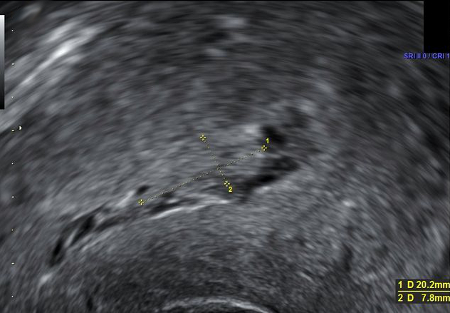

Ultrasound image showing retained product of conception within the endometrial cavity (measuring 20 x 8mm) in a woman with secondary PPH. The image was taken on day 22 post-delivery

Du R, et al. BMJ Case Reports CP 2021;14:e245009; used with permission